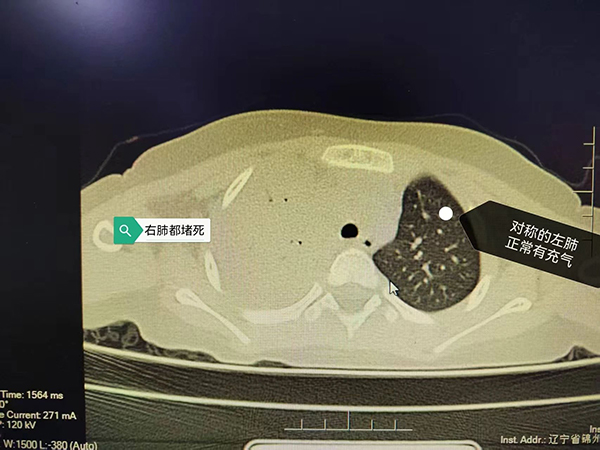

近日,我院小儿呼吸科收治了一名4岁小患者,他因持续高热、咳嗽10天入院。入院前虽经很多治疗,但病情仍逐渐加重,来诊时血常规显示白细胞高达2万(20×10⁹/L),炎症指标CRP 高达235.87mg/L,比正常值高出50多倍!胸片显示右肺炎,大约四分之三的右肺都被堵“没”了!我们立刻意识到这是一个特殊的重症肺炎!

入院后的胸部CT证实了我们的判断,病情不容乐观!热程已拖到10天,秉承着重症感染抗炎要重拳出击的原则,我们马上予以强有力的联合抗炎治疗,力求最快控制感染,并迅速安排了支气管镜术,在短时间内取得了病原结果,竟是“肺炎链球菌”这个经典的家伙!它的威力可不容小觑,只不过几天,小朋友的肺子就被啃成了“筛子”!

早期可见肺纹理增强或局限于一个节段的浅薄阴影,之后可能会出现大片状阴影,占全肺叶或一个节段。少数患者出现肺大疱或胸腔积液。个别肺炎链球菌肺炎出现化脓性并发症,可出现肺实变区的坏死病灶(看起来像是肺子成了筛网),或出现支气管肺胸膜瘘或大小不等的脓肿等。